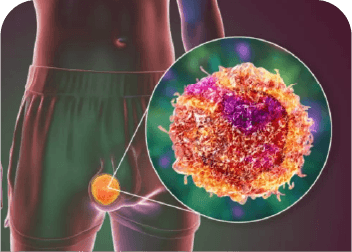

Tumor de Testiculo

Masa anormal que puede presentarse en uno o ambos testículos; requiere diagnóstico y tratamiento oportuno.

Orquiectomía

Cirugía en la que se retira uno o ambos testículos. Se realiza por razones médicas como cáncer testicular, dolor severo o problemas hormonales.